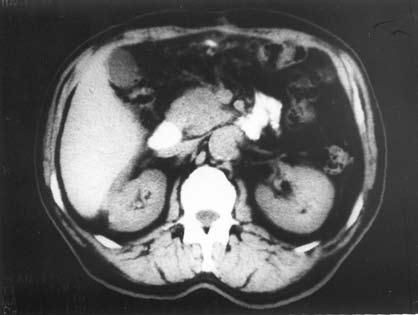

К сожалению, и специальные методы не во всех случаях позволяют решить рассматриваемую дифференциально-диагностическую задачу. Так, исследование крови больного на карбогидратный антиген (СА19-9) и раковый эмбриональный антиген (РЭА) дает отчетливо положительный ответ лишь при достаточно больших размерах опухоли, часто в неоперабельных случаях. Исследование ПЖ с помощью ультразвука или на компьютерном томографе дает увеличение размеров железы, в особенности ее головки, и при ХП, и при раке, а также выявляет очаговые образования тех или иных размеров, причем для рака более характерно одиночное гипоэхогенное образование, а при ХП поджелудочная железа чаще изменена диффузно, она гиперэхогенна (более плотная), содержит множественные кальцификаты (см. рис. 137–139), хотя точно дифференцировать характер очагов удается далеко не во всех случаях. Трудности дифференциальной диагностики ХП и рака ПЖ по данным УЗИ и КТ иллюстрируют рисунки 142–145.

Рис. 144. Компьютерная томография. Рак головки ПЖ. На снимке видна гиподенсная бугристая опухоль головки ПЖ 4x5 см (1)